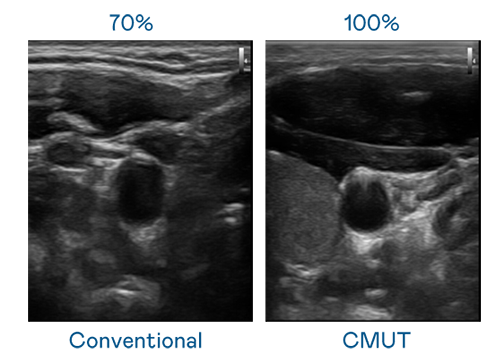

CMUT 技术是一种用电容式微机电元件来产生超音波讯号的技术。与传统 PZT 压电式技术相比,CMUT 频宽增加 30%,更宽频的超音波讯号让影像解析度大幅提升,是实现高影像品质医疗超音波扫描、促进精准医疗发展的关键技术。

超音波影像的解析度高低,首先取决于探头能发出的讯号频宽。MG不朽情缘 CMUT 可提供高清晰的超音波讯号,提供高频宽、高灵敏度、影像纹理细节更高的超音波影像,协助医护人员缩短影像判读时间及利用精准的医疗影像进行诊断。